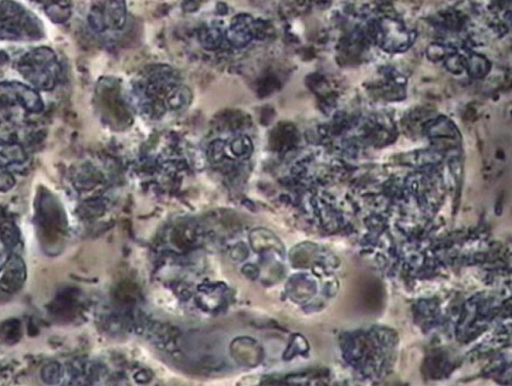

位相差顕微鏡

位相差顕微鏡とは、

光学顕微鏡の一種で、

口腔内で活動する細菌を確認できる

特殊な顕微鏡のことです。

その特殊性とは、光線の位相差をコントラストに変換して観察できるところにあり、標本を無染色・非侵襲的に観察することができるのです。

この検査を行うことで、歯周病の原因菌が特定でき、それにより歯周病の治療計画がたてられるようになります。

位相差顕微鏡検査では、まずお口の中に残っている歯垢をほんの少し採取します。

それをプレパラートに乗せてセットします。口腔内に存在する細菌の種類は500~700種類といわれています。

ですので歯垢1mgあたりの細菌数は1億個ともいわれており、歯垢は細菌の塊なのです。しかし、口腔内に存在する細菌すべてが問題ではありません。

細菌の量や密度が低く、菌の種類も少なく非常に静かな雰囲気のある像が正常菌叢です。

それに対し、悪い菌叢はいろいろな種類の菌が密集して菌が激しく動き回り、濁流のような像となります。

当院では、口腔内の細菌叢の存在や活動状況をリアルタイムで観察できる、イポナコロジー社製の位相差顕微鏡を用いて3200倍の高倍率で細菌叢を観察でき、さらに静止画や動画を記録できます。